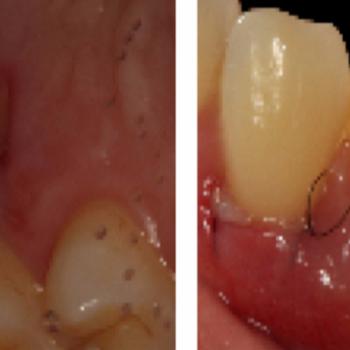

La cirugía mucogingival reconstructiva alrededor de implantes corrige los defectos de la morfología, posición y/o cantidad de encía queratinizada alrededor de los mismos. El documento que mostramos a continuación presenta el caso clínico de un paciente varón de 55 años de edad, exfumador de hace 2 años, con antecedentes de periodontitis crónica moderada generalizada y avanzada localizada tratada y, actualmente en fase de mantenimiento. El paciente no refería ningún antecedente médico de interés odontológico ni alergias conocidas.

El caso clínico es un buen ejemplo de cómo dotar de una buena cantidad de encía queratinizada unos implantes dentales con una emergencia en mucosa alveolar. De esta forma puede mejorarse la higiene periimplantaria diaria y disminuir así  las posibilidades de aparición de patología periimplantaria en un futuro.